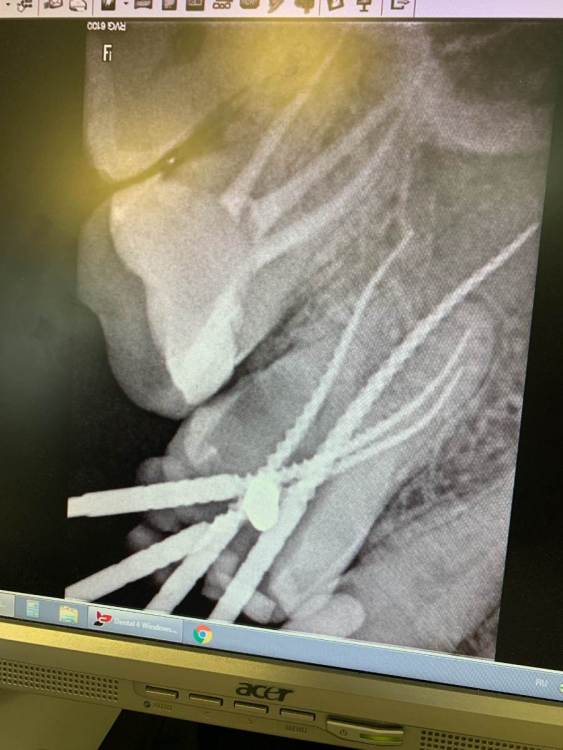

denrusof Опубликовано 10 сентября, 2021 Поделиться Опубликовано 10 сентября, 2021 Помогите пожалуйста советом что делать с 16?, терапевт предложила 3 варианта: 1. Депульпировать+ пломба 2.Депульпировать+ культя с коронкой 3. Удаление+ имплантирование Спасибо за ответы. Ссылка на комментарий

denrusof Опубликовано 12 сентября, 2021 Автор Поделиться Опубликовано 12 сентября, 2021 Сегодня депульпировали 4 канала + временная пломба, через 10 дней повторный прием на котором будет решать пломба или коронка Ссылка на комментарий

annda Опубликовано 12 сентября, 2021 Поделиться Опубликовано 12 сентября, 2021 (изменено) Я -за коронку,тем более,что напротив будет тоже коронка из керамики на имплантате. Если пломба,то только с перекрытием всех бугров не менее 2 х мм.Можно и титановый штифт поставить,с целью герметизации СИЦ цементом устьев всех каналов(а не только того,куда штифт воткнут) Изменено 12 сентября, 2021 пользователем annda Ссылка на комментарий